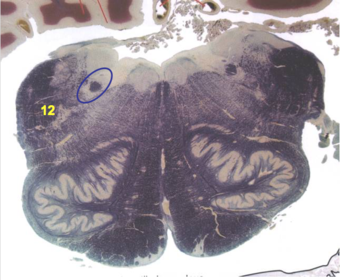

| CN IX | |

| Inferior cerebellar peduncle | |

| Inferior olivary complex | |

| Dorsal cochlear nucleus | |

| Inferior vestibular nucleus | |

| Medial vestibular nucleus | |

| Spinal nucleus of V | |

| Spinal tract of V | |

| Medullary pyramids | |

| Solitary nucleus | |

| ALS | |

| Medial lemniscus | |

| Medial longitudinal fasciculus | |

| Ventral cochlear nucleus | |

| Anterior spinocerebellar tract | |

| Central tegmental tract | |

| Olivary internal arcuate fibers | |

| Solitary tract | |